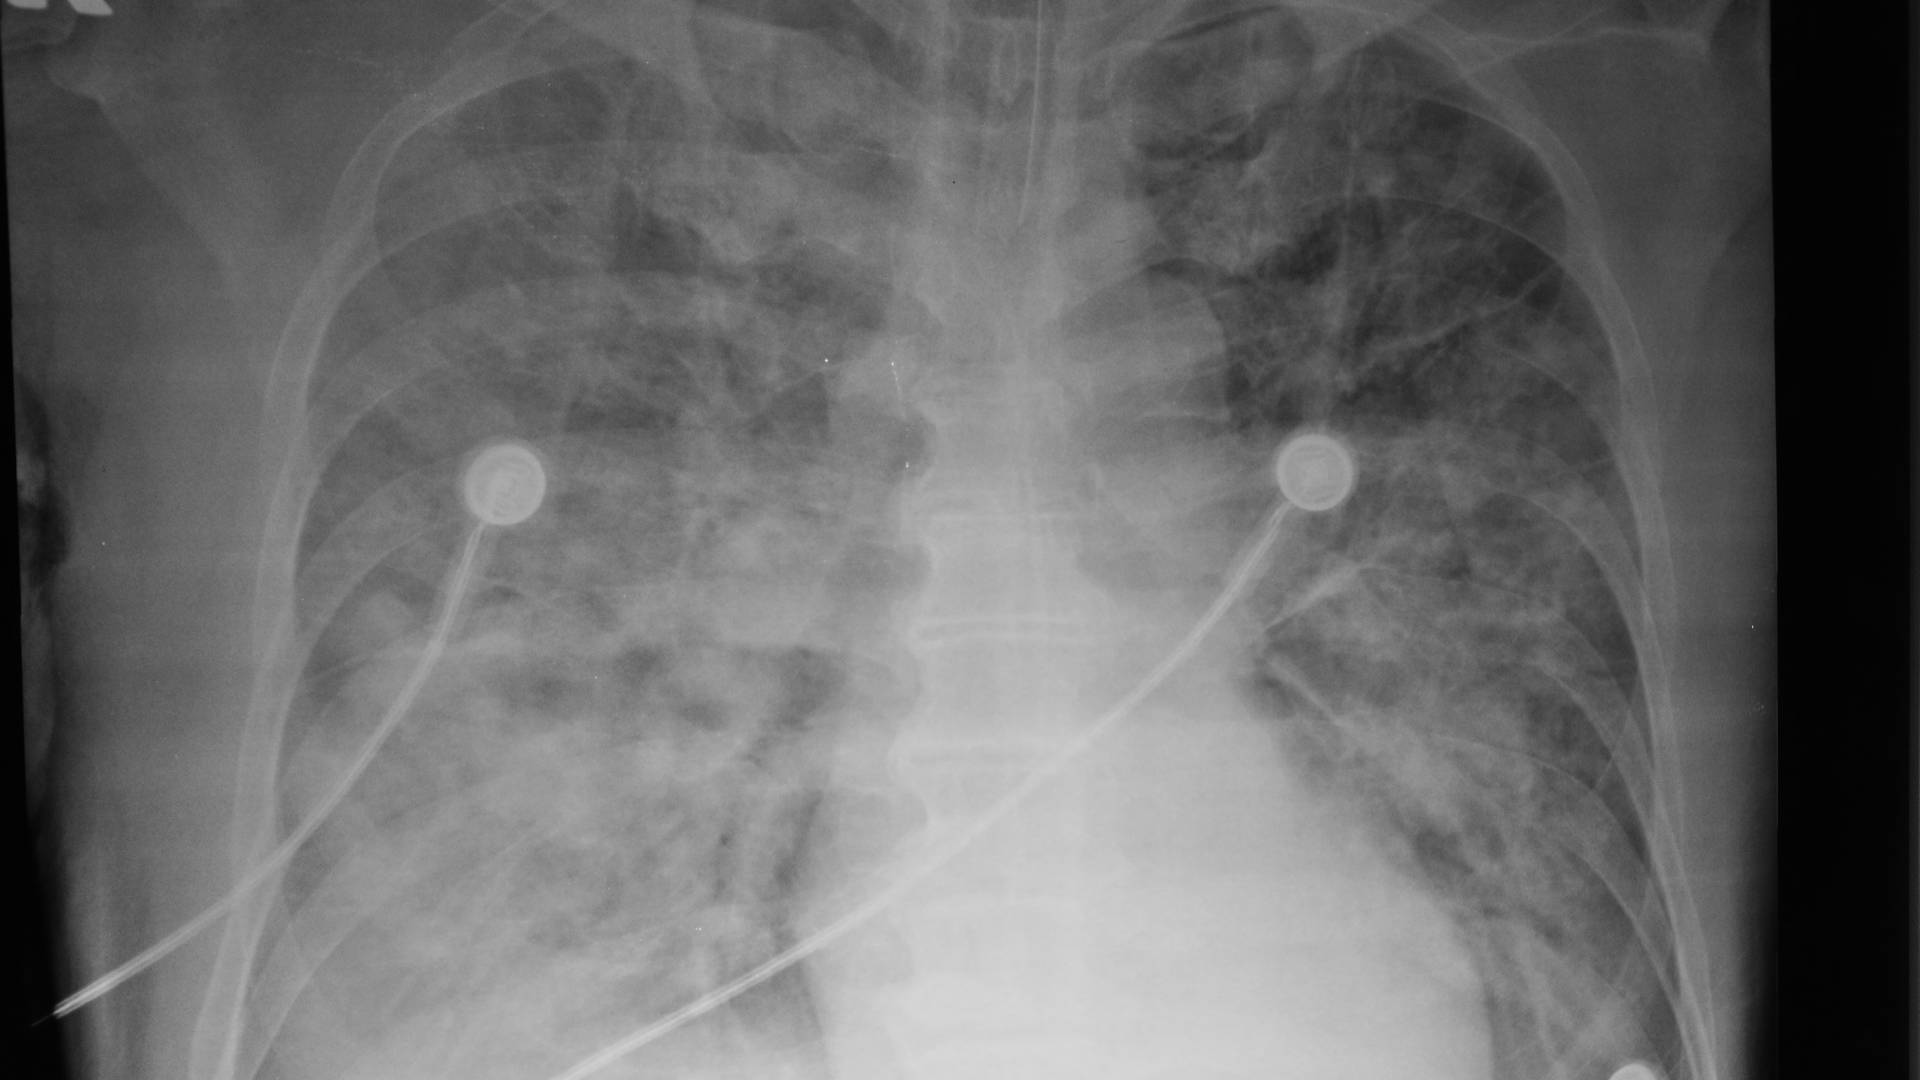

- Core inclusion criteria: Intubated and mechanically ventilated; acute onset; bilateral infiltrates consistent with pulmonary oedema; PaO2/FiO2 ≤300 (ALI) and ≤200 (ARDS); no clinical evidence of left atrial hypertension (pulmonary-artery wedge pressure ≤18 mm Hg if measured).